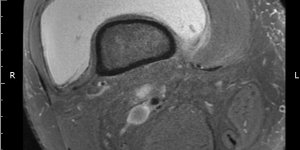

(2016) Patient (male) aged 44 attends physical therapy department with right knee pain. He gives a 5 year history of knee pain. He has noticed on and off swelling in the right knee. The clinician notices high BMI. On knee exam, there is slight swelling noticed on the knee. ROM is full with slight tightness at end range flexion and extension. [...] Read more

Knee – Bucket Handle Tear & ACL Tear

Case History 32 Year old female Felt a pop in the knee when doing box jumps. Developed knee pain with slow swelling. Improved a couple of weeks later. 5 Months later while doing weighted lunges, knee popped again. Improved again but residual pain persisted. Continued to do cross fit. Referred to MSK Physio by GP. Examination Mild end range flexion [...] Read more